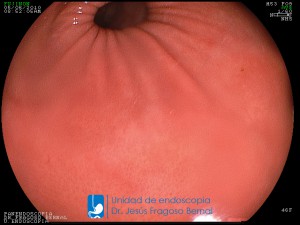

La Unidad de Endoscopía fue creada en 2002 por el Dr. Jesús Fragoso Bernal, es pionera en el estado por la utilización de la tecnología más avanzada, que nos permite ofrecer servicios integrales de diagnóstico y tratamiento para las enfermedades del aparato digestivo.

"La Unidad de Endoscopía se ha caracterizado por un progreso continuo desde su inicio marcando la pauta en los procedimientos endoscópicos en el estado de Tlaxcala y estando siempre a la vanguardia tecnológica."